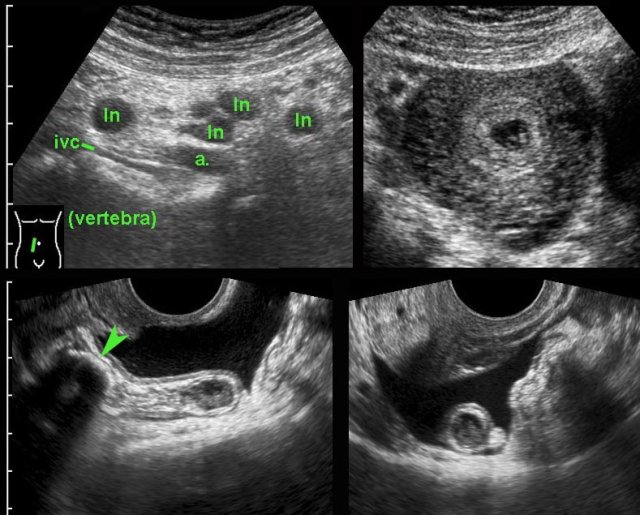

A young, early pregnant woman presented with acute deep pelvic pain.

US demonstrated enlarged mesenteric lymph nodes (ln) and an intact intra-uterine pregnancy.

The appendix was not visualized. (ivc = inferior vena cava, a = iliac artery).

TVUS easily demonstrated a 12-mm, inflamed appendix harbouring a large fecolith (arrowhead).

The appendix was in pelvic position and surrounded by free fluid.

There was no perforation at surgery.

In this obese, 3 weeks pregnant woman, transabdominal US visualized an dubiously abnormal appendix (← ?).

TVUS showed a dilated, pus filled, inflamed appendix in deep pelvic location.